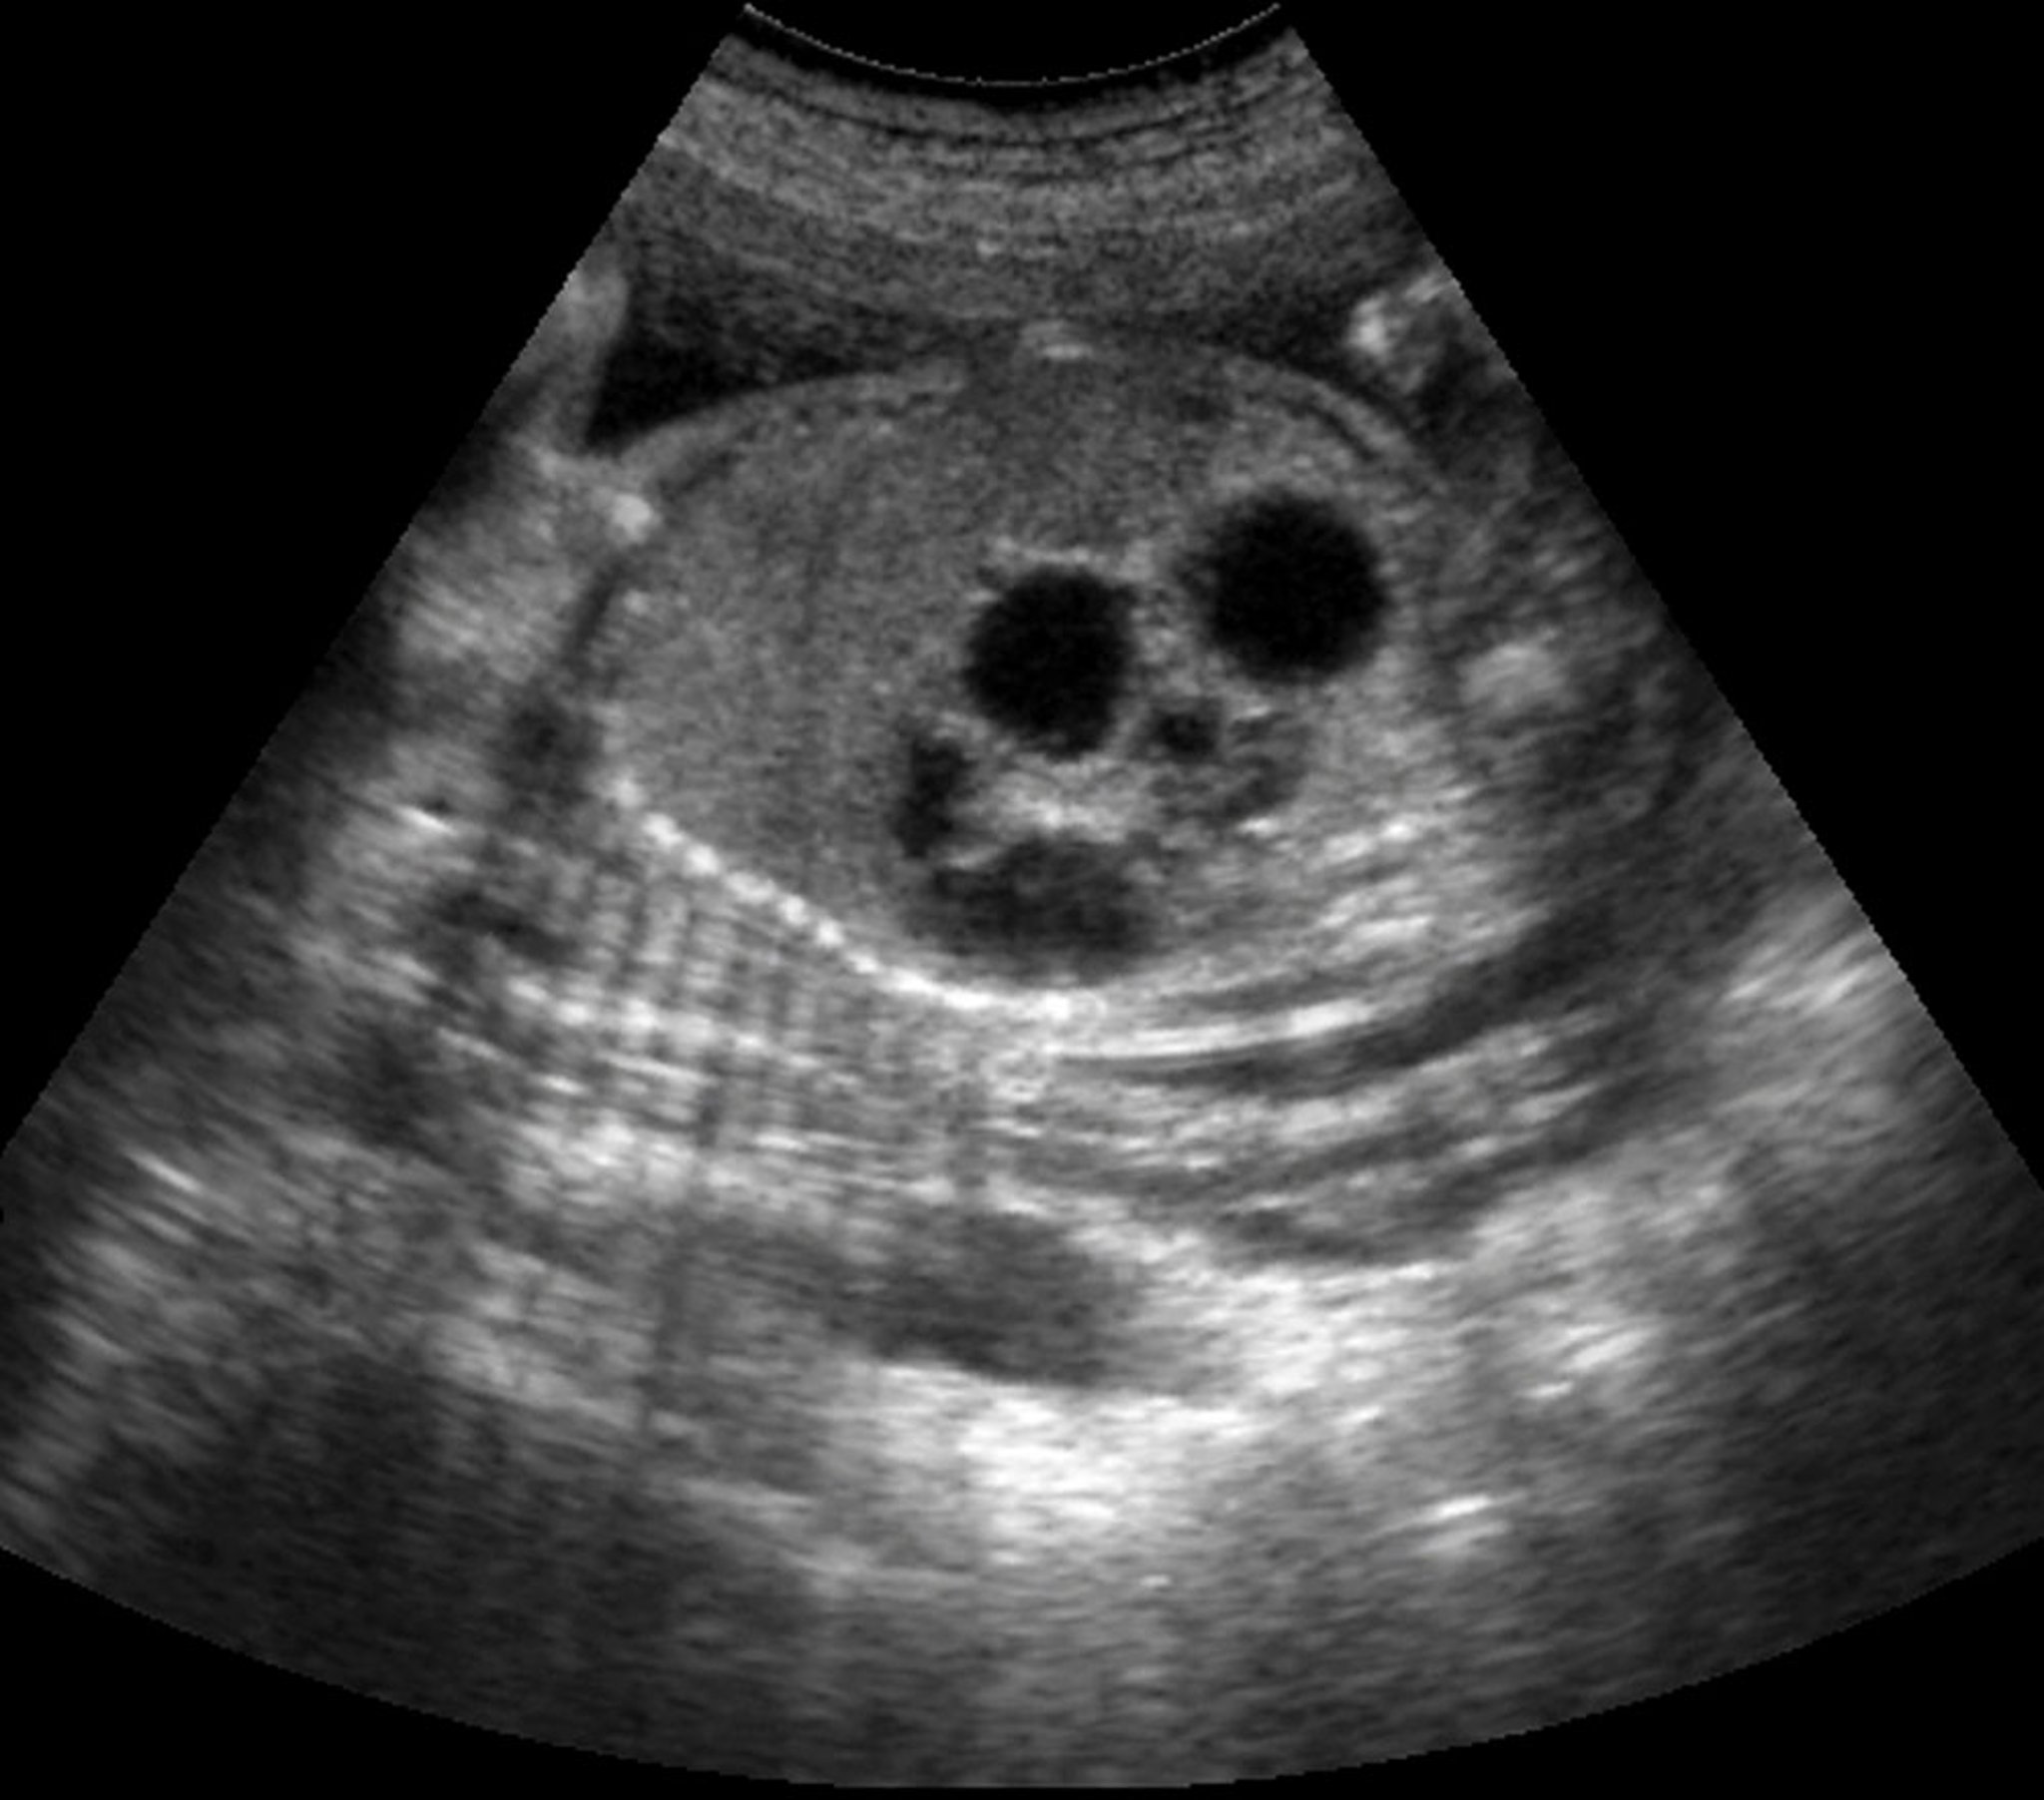

双重气泡效应(超声)

该超声显示胎儿十二指肠闭锁的双泡征。